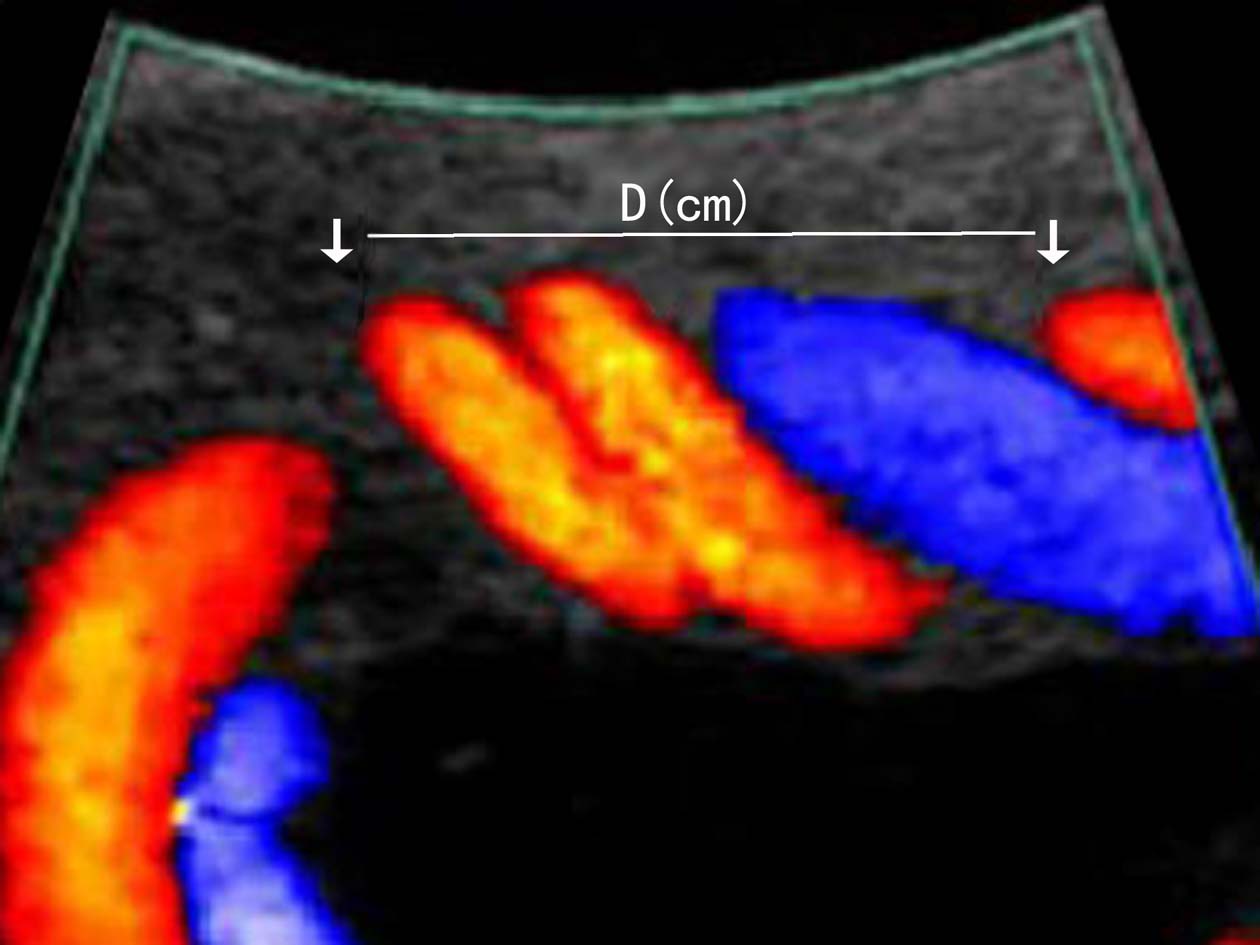

超声显像检查可通过测量脐带纵轴切面上两个螺旋之间的距离来计算螺旋指数,评价脐带螺旋稀少或脐带螺旋过度(图5)。超声多普勒血流显像检查时脐带过度螺旋显示血管绞合明显,脐带血管内径缩小、血流加速;螺旋稀少时显示脐带血管平直,绞合稀少。频谱多普勒检查可以对脐带动脉的血流进行评价。

图5脐带螺旋异常